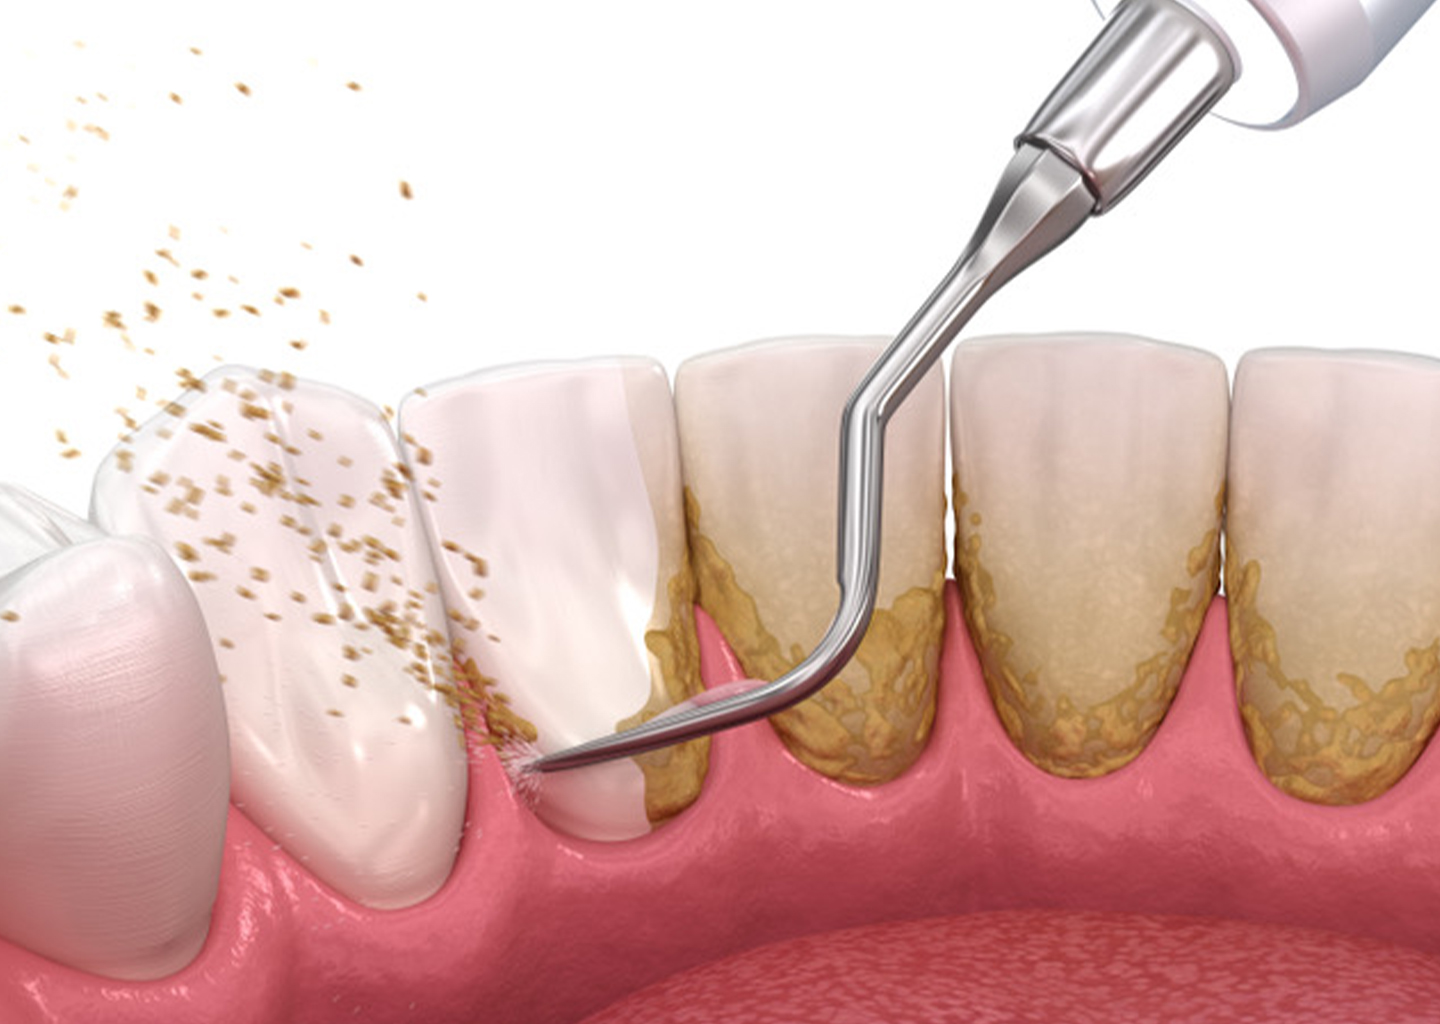

Zahnerhaltung

Unser Ziel ist es Ihre Zähne so lange wie möglich durch Prävention, Diagnostik und Therapie gesund und stark zu erhalten.